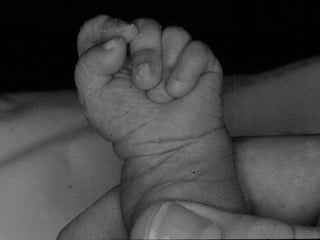

Edward syndrome (extra 18)

• Head – prominent occiput, narrow bifrontal

• Face - Low set pixie ears, small eyes, small

nose,mouth,chin

• Clenched hands, overlapping fingers, nail hypoplasia

• Rockerbottom feet, short halluxes

• Narrow hips

• Genital

• Short sternum

• Cardiac, kidney, limb, CNS

• Growth

• Feeding

Morbidity and mortality

• “lethal” profound developmental impairment